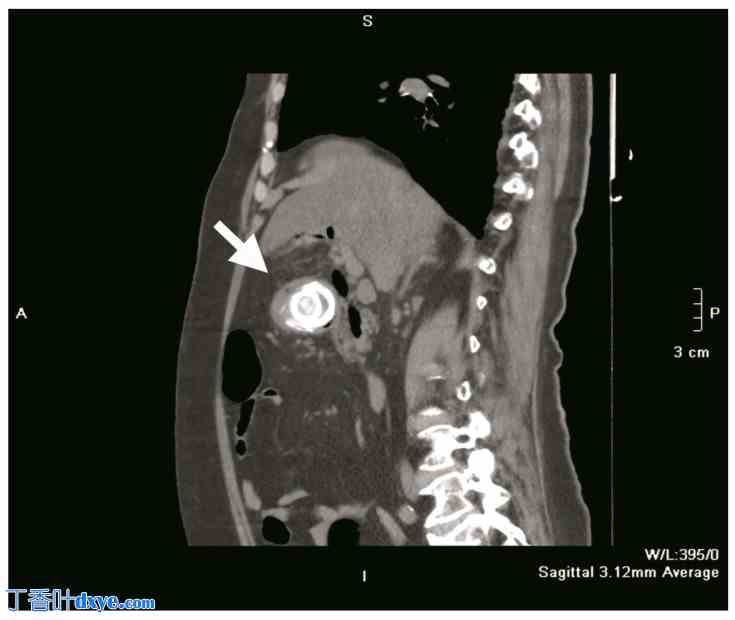

图 2.

矢状面 CT 扫描显示一颗胆结石(白色箭头)嵌在十二指肠球内。